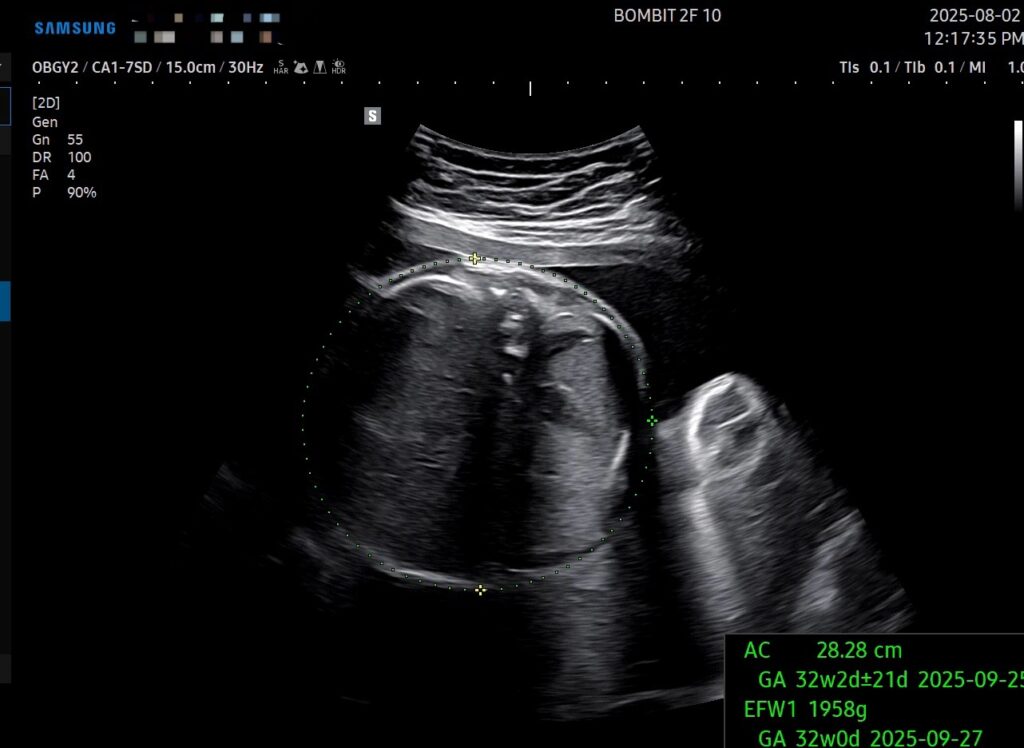

29주 6일차의 초음파인데, 몸무게, 배 둘레, 다리 길이 기준으로 주수는 약 32주로 나온다.

예상 몸무게는 1.958kg인데, 마미톡 주별정보의 30주차 적정 아기 무게는 1.4kg이라고 나온다. 아무리 초음파 측정이 오차범위가 있다지만 단비가 과도하게 큰 건 맞는 듯 하다 ㅜㅜ